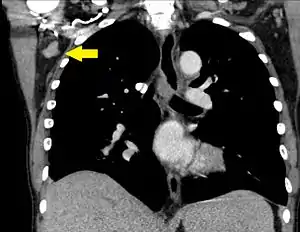

| A CT scan of axillary lymphadenopathy in a 57-year-old man with multiple myeloma. | |